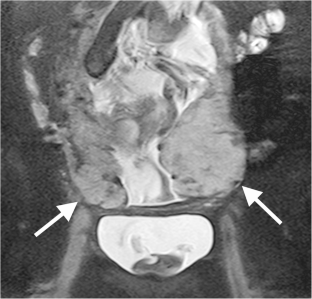

Fig. 1

Fig. 2

Fig. 3

Fig. 4

Fig. 5

Fig. 6

Fig. 7

Fig. 8

Fig. 9

Fig. 10